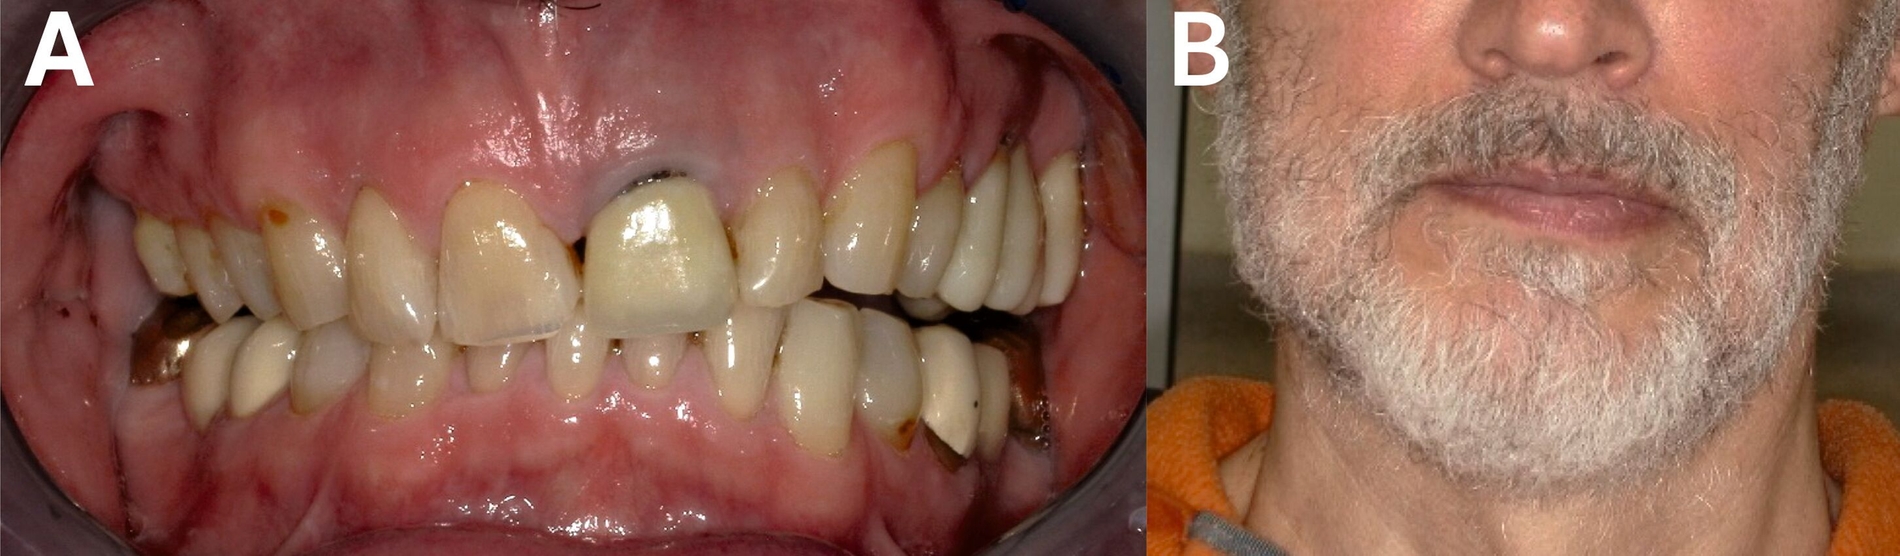

In der klinischen Untersuchung wies der Patient einen isolateral seitlich offenen Biss sowie eine Laterognathie zur Gegenseite auf, die sich in einer deutlichen Asymmetrie des Gesichts äußerte (Abbildung 2).